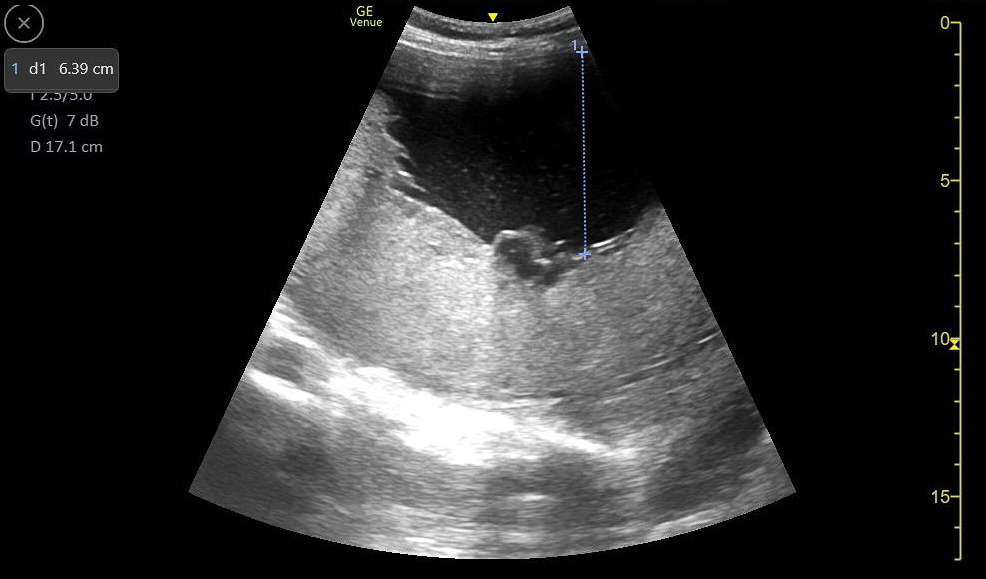

- Greatest Vertical Pocket (GVP).

- After scanning the entire uterine cavity systematically (mowing the lawn), find and measure the single deepest pocket of anechoic amniotic fluid perpendicular to the bed with no fetal parts present. The probe marker should be pointing to the patient’s head.

- Normal ranges from 2cm – 8cm

Figure 37. A normal greatest vertical pocket of amniotic fluid. Note the calipers measuring the deepest pocket of amniotic fluid not containing any fetal parts.